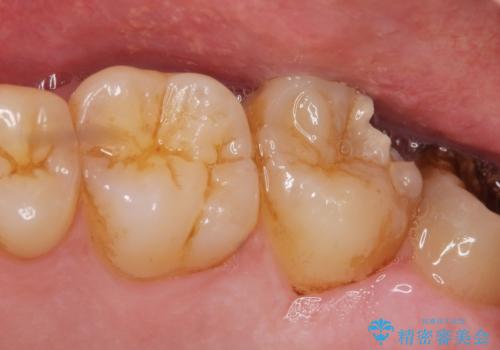

[フルジルコニアクラウン] 老朽化した銀歯を白く

![[フルジルコニアクラウン] 老朽化した銀歯を白くの症例 治療前](https://seimitsushinbi.jp/wp/wp-content/uploads/2020/05/095ef1aef9dfbbc03d4a7b2f7a38a13c-500x350.jpg?v=1588518714)